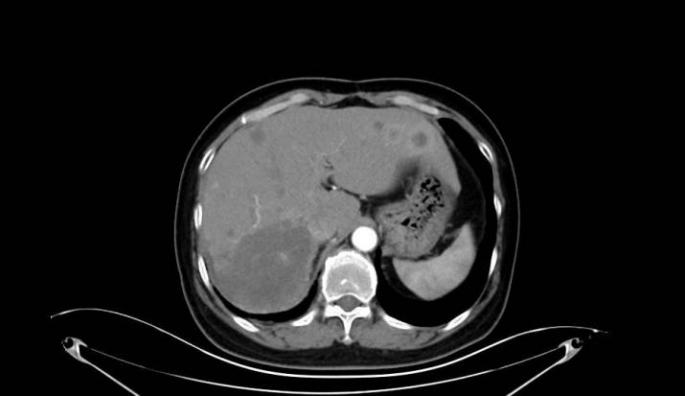

近日,哈医大肿瘤医院胸部放疗四病房尹航教授团队运用前沿空间分割放疗(SFRT)技术,成功为一名胸腺恶性肿瘤肝转移患者实施精准治疗。患者肝脏转移瘤直径由12cm显著缩小至 4.3cm,症状全面缓解,生活质量大幅提升,充分展现SFRT技术在晚期肿瘤治疗领域的突出优势和临床价值。

患者此前接受多种治疗方法,病情仍持续进展。2025年9月复查显示,肝脏转移瘤已增大至12cm,伴随明显腹胀、腹痛等症状,严重影响生活质量。面对这一复杂病情,传统治疗手段效果有限,肿瘤进展难以控制,患者一度陷入治疗困境。

治疗期间,患者肝脏转移瘤从12cm迅速缩小至7cm,体积锐减超四成。治疗后3个月复查,巨大转移瘤已缩小至4.3cm,体积缩减近三分之二,患者生化指标大幅好转,体重较治疗前显著增加,疼痛症状完全缓解,饮食、睡眠与日常活动逐步恢复正常,生活质量显著提升。

左:治疗前 中:治疗中 右:治疗后三个月